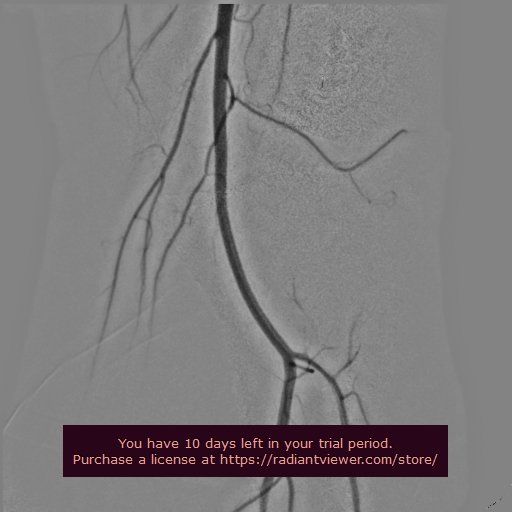

SUPERFICIAL FEMORAL ARTERY ANGIOGRAM

POPLITEAL ANGIOGRAM

BELOW KNWW TRIFURCACTION